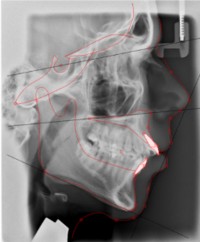

Foto skeletal utveckling

Utvärdering av växt med hjälp av superponering.